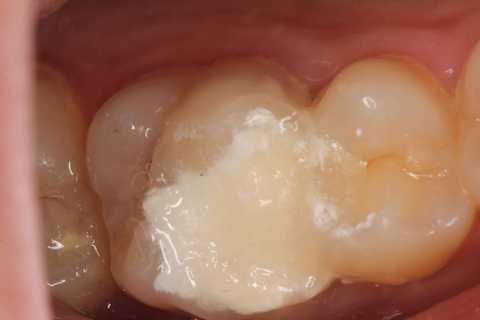

20代女性、左上6、自発痛+

確かに窩洞内はプラークまみれで、露髄しているので痛いのだろうな。。と思わせる。

でも、露髄していようが、感染歯髄だろうが、歯髄息肉だろうが関係ない。歯髄があるところまでα-TCPセメントで塞げば、痛みも止まるし、歯髄を保存できる。

次回はちゃんと充填して歯を作るからねーと言って仮封して帰ったが、痛みが止まったので、もうこれでいい!と勝手に判断して来ない。電話をかけても出ない。知らんわ、、

では時系列でどうぞ